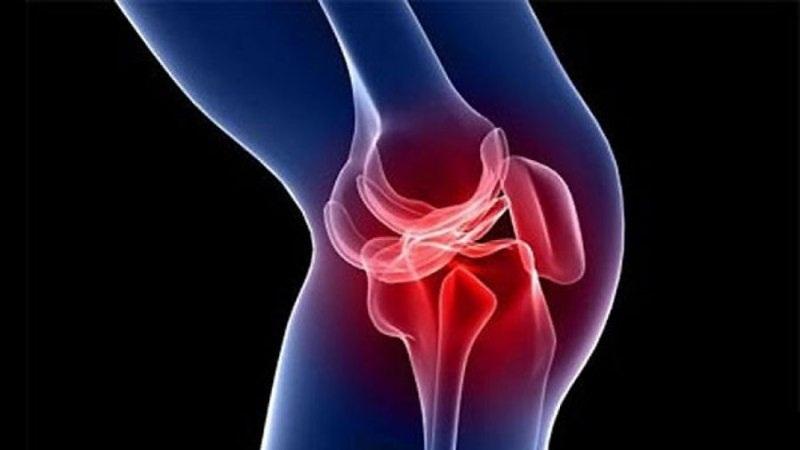

Хирургическая операция осуществляется через небольшие проколы кожи с использованием специального инструмента – артроскопа. Его диаметр составляет всего четыре миллиметра, а на конце установлена видеокамера.

Артроскоп вводится в полость сустава и передает изображение на экран, что позволяет хирургу оценить состояние и восстановить внутренние структуры. После диагностики, под контролем артроскопа и с помощью специализированных инструментов, выполняются все необходимые процедуры.

Поскольку соединить поврежденные концы крестообразной связки невозможно, врач удаляет поврежденную связку и создает новую. В процессе операции могут быть использованы собственные сухожилия пациента или искусственные материалы.

Для восстановления связки обычно применяются собственные связки из области надколенника или сухожилия полусухожильной мышцы.

Во время формирования недостающих структур врач фиксирует новые ткани с помощью винтов и пуговиц. После завершения операции и в процессе реабилитации трансплантат врастает в кости, полностью заменяя крестообразные связки и выполняя их функции.